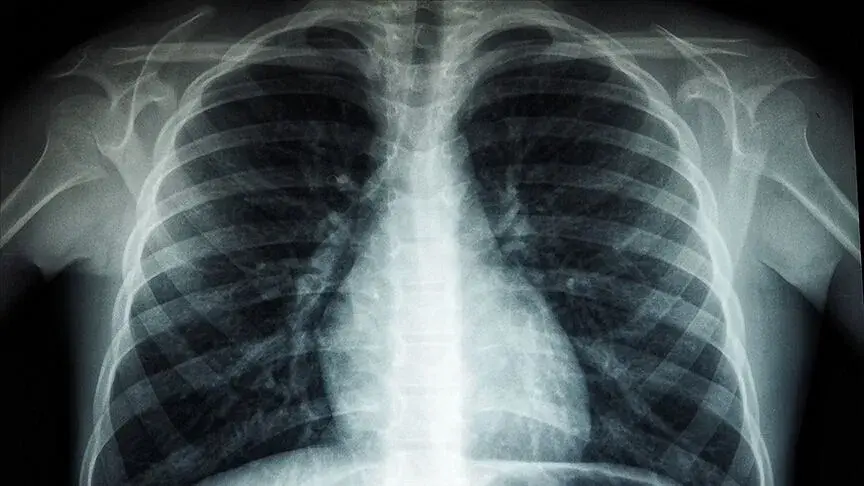

Kars'ta mucizevi bir tedavi ile 82 yaşındaki Ahmet Çağır, yıllardır bağımlı olduğu solunum cihazından kurtulmayı başardı! Oksijen cihazı olmadan adım atamayan bir hasta, şimdi yürüyüş yapabiliyor ve egzersizlerle dinç kalıyor. Kafkas Üniversitesi Sağlık Araştırma ve Uygulama Merkezi'nde gerçekleştirilen bu tedavi sayesinde Çağır, artık oksijen tüpüne bağlı kalmadan günlük yaşantısını sürdürebiliyor.

Ahmet Çağır, yıllardır kullandığı solunum cihazı sayesinde yaşamını sürdürebiliyordu. Ancak son zamanlarda yaşadığı akciğer sorunları, hayatını adeta felç etmişti. Kars’ın Sarıkamış ilçesinde yaşayan Ahmet Çağır, 2019 yılında geçirdiği akciğer enfeksiyonu nedeniyle hastaneye başvurdu. Ancak, sadece solunum cihazı ile dışarı çıkabilen Çağır’ın hayatı, Kafkas Üniversitesi Sağlık Araştırma ve Uygulama Merkezi'nde gördüğü tedaviyle değişti. Göğüs hastalıkları uzmanı Dr. Çağrı Atasoy, Çağır’a uyguladığı tedaviyle, oksijen cihazına veda etmesini sağladı.

Ahmet Çağır’ın tedavisinin başlangıcı, Kafkas Üniversitesi Sağlık Araştırma ve Uygulama Merkezi'nde yapıldı. Interstisyel Akciğer Hastalıkları Konseyi tarafından yapılan tetkikler sonucunda, akciğer sertleşmesi olduğu belirlenen Çağır, kısa süre içinde antifibrotik tedavi alarak büyük bir iyileşme gösterdi. Dr. Çağrı Atasoy, Çağır’ın tedavisinde kullandığı karbonmonoksit difüzyon testi cihazı sayesinde hastalığının seyrini net bir şekilde gözlemleyerek, tedaviye başladıklarını belirtti.

Dr. Çağrı Atasoy, interstisyel akciğer hastalıklarının tedavisinde kullanılan yeni ilaçların artık bu hastalıkları kontrol altına alabileceğini ve hastaların iyileşme sürecini hızlandırabileceğini belirtti. Dr. Atasoy, “İnterstisyel akciğer hastalıkları, akciğerin sertleşmesiyle giden ve uzun yıllar tedavi edilemeyen hastalık grubudur. Ancak son yıllarda geliştirilen ilaçlar, bu hastalıkların ilerlemesini durdurmayı başarıyor. Tedavilerde kullandığımız karbonmonoksit difüzyon cihazı ve solunum cihazları, hastaların tedavisinde büyük rol oynuyor” dedi.

Hava kirliliği, sigara içme alışkanlığı ve yaşın ilerlemesi, akciğer hastalıklarının tetikleyicilerinden bazıları olarak öne çıkıyor. Dr. Atasoy, akciğer hastalıklarının erken teşhis edilmesinin, tedavi sürecini hızlandırabileceğine dikkat çekti. Yeni teknolojilerle hastalıkların teşhis edilmesinin yanı sıra, tedaviye yön veren gelişmiş cihazlar, hastaların yaşam kalitesini arttırabiliyor.